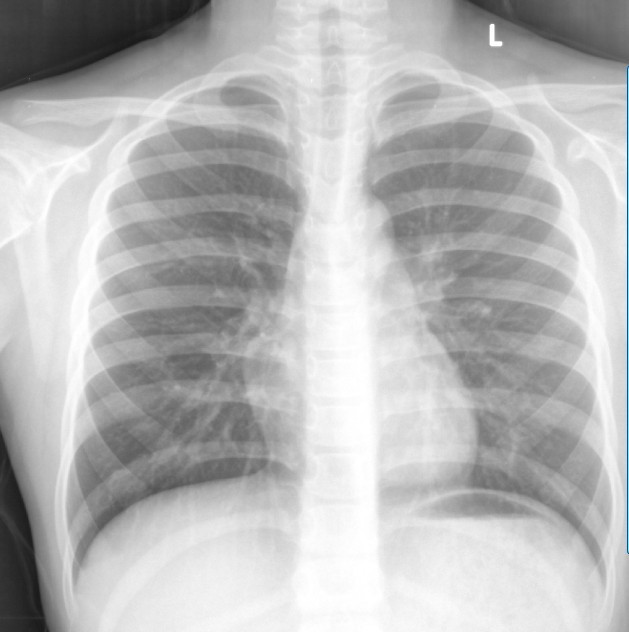

标题: X6883:体检

心影右侧部分稍凸起,是体位的关系吗?

正常

突出的较突兀,不好说是什么病变,还是建议进一步检查吧!

右心缘突建议彩超和ct除外心脏和纵隔病变

未见明确异常。

未见明确异常,结合临床,必要时心超检查。

胸部未见异常。

未见明确异常,结合临床,必要时心超检查